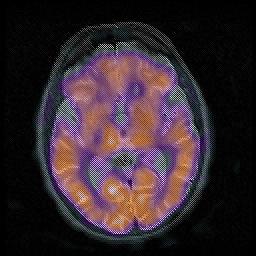

Huntington's Chorea, MR -- Slice #9

[Home][Help][Clinical] Slice 9